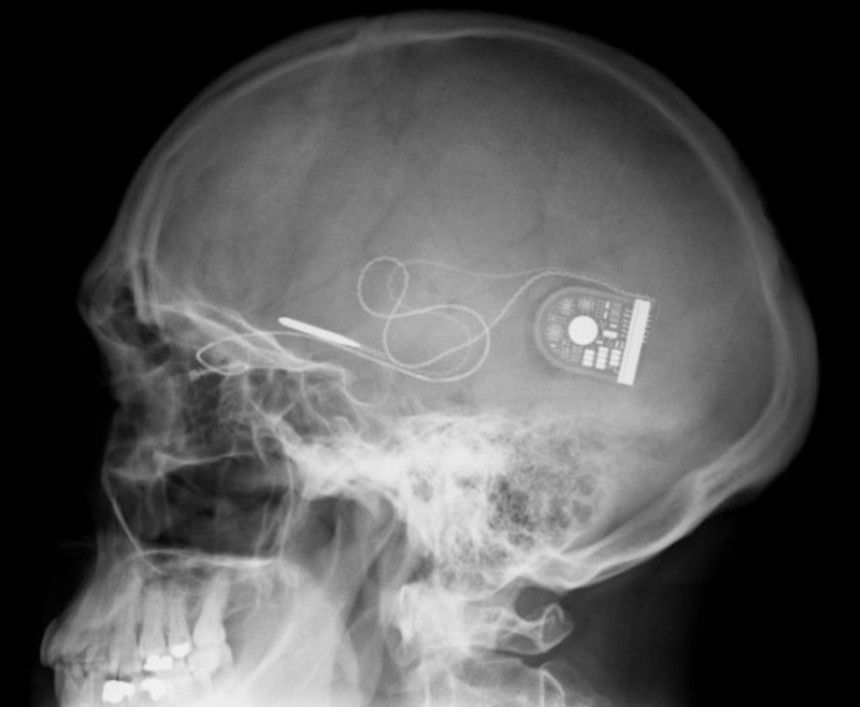

DARPAのプログラムマネジャー、ジャスティン・サンチェスによると、海馬と直接的に相互作用する人工神経装置を脳に埋め込むことで、陳述記憶を回復させることができるそうだ。この人工神経装置は脳に電気パルスを送り込むことで脳の働きを支援する。これまで、動物を使った実験では、短期間のワーキングメモリの拡張に成功しているという。

この計画は1憶回復装置の開発を目的としたもので、1億ドル(約100億円)の予算が投じられ、4年計画で行われている。ついに完成の時が近いようで、あと数か月以内に米軍の極秘研究チームが脳に埋め込み失われた記憶を回復させる装置に関しての発表を行うという。